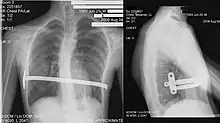

Coupe au scanner.

Le diagnostic est clinique, par l'examen de la déformation thoracique. On peut toutefois proposer la réalisation d'une tomodensitométrie thoracique, permettant le calcul de l'index de Haller, évaluant de manière objective la sévérité de la déformation et permettant de rechercher une compression cardiaque, trachéale ou œsophagienne. Des explorations fonctionnelles respiratoires évaluent l'impact de la déformation sur la fonction pulmonaire, et une épreuve d'effort recherche l'impact sur les capacités d'effort.